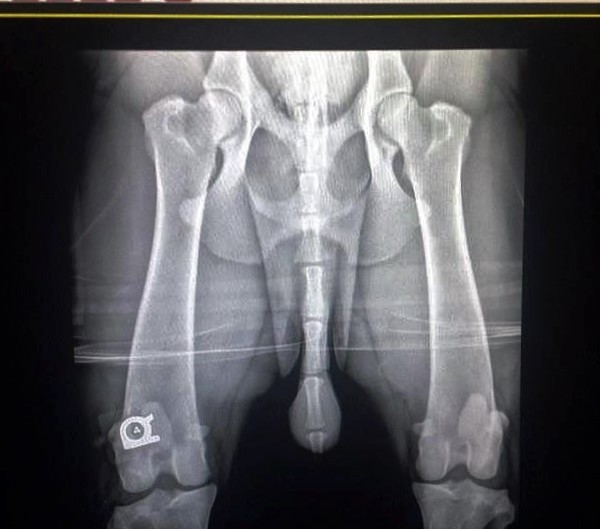

OFA Hips - Excellent - AK-15263E71M-PI

OFA Elbows - Normal - AK-EL2937M71-PI